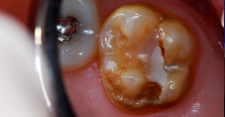

A 7-year-old presented with a malformed, sensitive molar.

Figure 14

The tooth was prepared for a restoration with an RMGI bioactive ionic resin-based composite.

Figure 15

An orthodontic matrix band was placed and a self-etching bonding agent was applied.

Figure 16

The bonding agent was light-cured.

Figure 17

Finished RMGI bioactive ionic resin-based composite restoration.

Figure 18